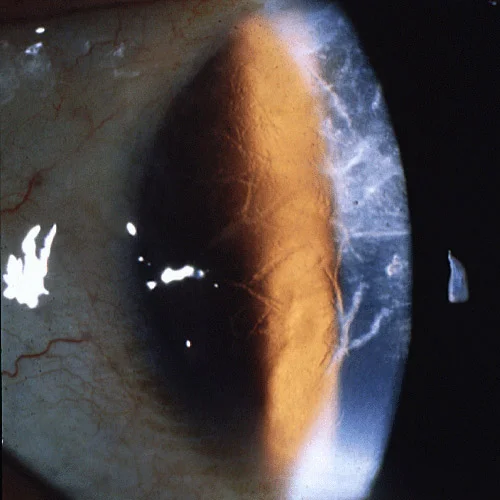

Episode 12: Macular Dystrophies